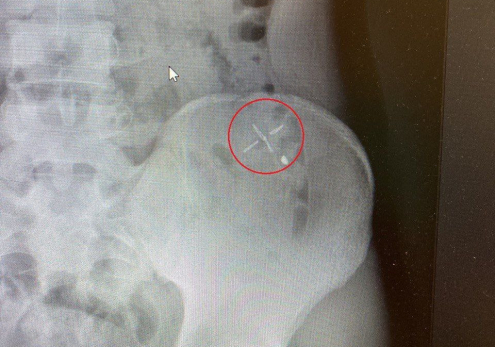

Российские врачи спасли 19-летнего парня с металлическим обломком в животе. Все произошло, когда молодой человек косил на даче траву, не используя спецодежду. В процессе работы от садового триммера отскочила небольшая часть и вонзилась в живот.

Как сообщает Минздрав, пациента доставили в Каширскую больницу с кровоточащей раной. Чтобы достать обломок врачи решили проводить оперативное вмешательство.

- Мы провели исследование раневого канала, затем удалили инородное тело, которое прошло через несколько слоёв кожи, и наложили швы. Еще несколько миллиметров и могло произойти повреждение брюшины, которое грозило травмой внутренних органов, - рассказал заведующий хирургическим отделением Александр Страчук.

фото: Минздрав